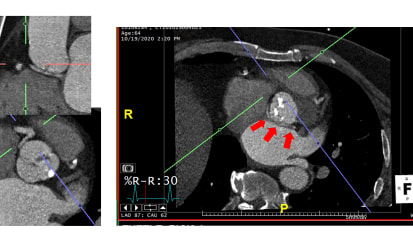

Good morning. Thanks for attending cardiac grand rounds at the heart hospital today. Uh, this is Deepak. Tell rage on talking today on the topic of coronary access after trans catheter based story valve replacement. Hi. This is a two part grand rounds. I'll be giving 20 to 30 minute talk on accessing the coronaries after Tavern, which I think is a broad interest to the general population of everyone putting catheters in the heart and anyone ordering catherization test. And then Paul Mahoney is gonna talk afterwards on controversies in bicuspid valve disease. He's at a meeting now, and I actually have to run the meeting during the second half. So we agreed to fill in for, ah camper grand rounds, and I hope this will be interesting. Relevant disclosures way have had the good fortune of having access to all the three major, commercially available Taber platforms. Now that's Medtronic, Edwards and load this and we've been involved over the years and trials with a number of other platforms in various stages of development. Um, there's a ton of animations in here, and some of them run a little bit slowly so towards the middle of the portion of the program. I'm gonna actually come out of power point and just play them, uh, through a blank PowerPoint slide that seems to run faster. What I'm showing you here is three separate images. One on the far left is a surgical valve. In the middle is a Medtronic core valves. And on the right, you can make out the outline of a SAPIEN Edwards SAPIEN valve, these air, three valves in aortic position and the point of these slides and I'll play them again as we dio, is that, uh, we have become used to an increasingly wide array of complex technologies and coronary access. You think about augmentation devices like the impeller device, you think about IV's catheters, rotational and orbital a threat to me. You think about the generations of stents. We have the complexity of bifurcation, stenting and coronary physiology measurements. As time has passed, what we've evolved of, what we can do in the coronary circulation has gotten more complex. And with that challenge, for example, with an impel a catheter across the aortic valve or with a valve in place, there could be an atomic obstacles that are not in president. A normal circulation that we have to work around and think about guide selection. And we've become increasingly adept at that. Regardless of what kind of valve you have in the aortic position, there's a potential for interaction with the coronary Ostia. And so these techniques are meant to be sort of broadly accessible across the different groups of platforms. And while we're used to, as Judkins said, when he developed a jail catheter engaging 90% of coronary Ostia unless interfered with by the operator with that guide on the first past in the current era, it really behooves us to be able to think about where we're trying to get what are the obstacles and what we need to do to modify our approach, depending upon what's in the way. And here in all three of these cells, you can imagine a situation in which is more difficult to cross, whether it's a surgical valve, the core valve or the Edwards found. All right, so if you think about now, there's obviously variability in the heights of coronary Ostia and in the world of Trans catheter based or valve replacement would carefully analyze this ahead of time and project where will the valve be relative to the coronaries? And there's two issues. One is the height of the coronary, and you see here the median hide the coronary artery has the possibility of interacting with any valve frame, and also, sometimes we deploy the valve frames higher or lower. There's an increasing movement to deploy. Deploy the valve higher to impinge less on the conduction system that has the potential to bring the valve plane in mawr interaction with coronary Ostia In addition to simply the height, which is easy to measure by C. T. The second factor is the effacement of the coronary. When the valve in place, how much space will there be between the entry point of the coronary ost IAM and the outer sections valve? Now you can see of the three valve. The core valve is going to be the one that virtually all the time overlaps of coronary Osti. Um, whereas your other um trans catheter valve may or may not interact directly, although there is always potential for it to make it so that our standard catheter choice has some interaction with the valve, and that has to be thought about if you think about the current era, This is data. Over the last several years, there's been a lot of publications looking at successive coronary angiography. And the good news is, in the vast majority of cases, about 9500% of cases across the Siri's theon graters were able to engage the coronary arteries. There obviously exceptions, but in general, coronary access is successful. If you look at UH, success rate of PC I in these patients again, it's relatively high, You know, in no technology form is the success rate 100% even when there's no valves in place. But here you see a high success rate and calculations of adverse outcomes because of inability to successfully performing PC, I show the number to be very low. But this is a point of of concern amongst cardiologists and interventional cardiologists, and so we'll focus on some techniques that air widely available to anyone around. First of all, understanding the shape of the valve where the potential obstructions are for the various valve platforms is important. We'll talk about that more detail. Here you see the core valve on top and the SAPIEN valve on the bottom, and you see, we can use a lot of different forms of imaging. We can do non selective angiography to at least identify the portion of the coronary. Ostia, as you see on the top, right? We can use T, E E and C T to get analysis again, not necessarily in the semi case, but when pre planning In a complex case, that's certainly reasonable to do. I have to admit, I don't really do a lot of that. Usually I get in the lab even for an elective case, and start by looking for the coronary. And my success rates have been high with. The techniques will talk about two other things this illustration makes clear, and I'm gonna focus some of my comments on the Medtronic core valve today off the three valve. That's the one that has had the greatest concern across publications in discussions on re access. I think we're very successful in re accessing with the techniques. I'll show you some of the slides I've put together here. I've taken video using a demonstration platform in the cath lab. I'll show you momentarily, but with this valve, let's look at two things. I think it behooves us all to recognize. One is usually at the level of the coronary. Ostia. The valve isn't sitting flush against the coronary. AUSTIN. There's a space between the frame of the valve and the coronary Austin. So usually we're poking through the frame of the valve and then engaging the coronary Austin separately. Also, the holes are 10 French holes, and most of us are using 56 French catheter. So there's plenty of space to get through the frame itself. And with the right techniques, we should be able to engage the majority of coronary to me, as I think of the analogy of what we're trying to do in the cath lab, these air to images that I think of one of these, uh, these nice fellows reaching through the bars of the jail to do something. And you see, they can use their dexterity and get through and manipulate something complex on the other side. And that's what we're doing is we're finding which bar is the closest bar to go through, passing through it and then doing what we need to on the far end and engaging grass is often described as like a fishing sensation right. You see the catheter stabilizing the position, and you can feel the tug of it when you don't have too much attention on the capital. In some ways, it's like strumming a guitar. If you're trying toe poke your pointer finger into the central hole of the guitar, you might strum up or down until you find the space. You think it is going to get you exactly where you want to be, and then you push your index finger through that space, and it's the same thing you're trying to do with feeling the cats that are getting in here. I already alluded to the fact that if you think about it, there are capacious and crowded sign a tubular junctions and depending upon which you're dealing with, that can affect the complexity of engagement. And in fact, as we've gotten better at putting in valve, we've developed techniques and participate in techniques like the basilica Technique, where we create a laceration in the valve again. The analogy here and this is not the point of today's talk. It's just to show you there's a lot of creative things we do snorkeling stents above valve, creating tears in old leaflets on old prosthetic valves, and we put a new valve in and you can imagine if there was a shower curtain separating me from the audience and I was trying to talk to everyone. It will be hard to talk through that. But if I took an Exacto knife and made us slice through it and it folded open, then you could imagine us having a better communication. And that's what we're doing with this technique. And so we actually use catheters without an open procedure to open up a coronary. Often in those cases where we pre predict that they will be because of a crowded son, a tubular junction area, um, difficulty accessing the coronary. And this is what that actually looks like with the two most often used platforms. Religion. So two years ago, there was a nice article in Jack, and at that point this was really cutting edge discussion about coronary access and PC I after trans catheter aortic valve replacement. Since then, there have been a lot of different discussions, and this paper came out with some nice algorithms. Um, remember when this first came out, we hung them in the castle but beach and would have this available for anyone that needed it well long ago. Took those down because Manchester, actually fairly simple. If you're using a Judkins guide, which is effectively done by putting in, for example, of core valve is narrowed the size of the aorta. And so you downside by 0.5. Whatever Katherine you would normally initially go to you can certainly often get it with the standard catheter. But if you're having difficulty going down from a jail, four to a jail 35 to potentially be helpful in the algorithm has more listing there. There's also an android and iPhone app called the Cast Taber Aid. You can easily download and has nice videos of a lot of information on this, as well as the algorithms in place for those that might find that help. As far as equipment we really use the standard equipment we have E. C. I wires, guide catheters and under sizing by a half centimeter can often help guide extensions could be very useful using your J wire to point yourself in the right direction when you first engaged and then coronary balloons to track if needed, we'll go into this in more detail, actually, for a second, like I said, coming out of power point. So what we're gonna look at in the next couple of flies is early on because, as I said, we've. But only then thinking about the basis. Of course not. We're trying to develop a heart way models, models, a little beating pump. It's all made of plastic, so you can actually see the pump feeding. You can see the valve with your eyes that sits on the table that has a simulated radio access and assimilated them a criminal act. And he looked. You can actually see your catheters moving through it, and you can simultaneously floro it so on one of the opportunities that brought it down. But I'm going to show you a slide I made with floral clips of engaging the coronaries and with with iPhone video of the model itself so you can see outside of for what it looks like. I think you'll find this interesting. Um, the other thing I would tell you is that funny? When I when I was starting, I was hoping to make a slide presentation showing tricks success you'll see from some of the engagement, but actually, a lot of the standard catheters found their way into the coronary very quickly. And so that was. That was funny from my viewpoint, because I was trying to prove it was difficult with the standard catheters and easier with intelligence collected catheters. And it turned out it actually wasn't too hard with either way, thank you. So this is the model. If you look at the model here, it's in the box. It has fluid in it. There's what looks like a radio access and the femoral access. There's a beating pump, and if you look, this is the valve Opening and closing as we go through the aorta is in this view oriented to the left and that little beating pump. Heart is oriented to the right, and you can engage catheters and get through the frame and do exactly what we do in real life. So now let me show you some some attempts. An engagement. I flipped it now because someone's photographing from the opposite side while I'm pseudo scrubbed in the pump is to the left. That's the simulated left ventricle. The valve is opening and allowing blood to go out the order to the right. Picking up towards the top is the right coronary artery, and sticking down towards the left is the left main coronary artery. So as we go through these images, in each case, I'll show you a floral images. Well, here you can see a moving floor. Oh, the only thing you can actually see moving here is the outline of the cardiac shadow at the bottom. There, you can see the valve frame in place. So let's look at some techniques. So here we're gonna see an engagement with a standard with a standard J L four catheter and you see the catheter moving up through the pretend aorta tracking over a J wire and you'll see that the first goes up. It really goes into the right neo cussed there of the new valve on the right side. And of course, this is a jail catheter. I'd like to move my way over to the left main coronary artery. The way to do that is what you just saw. There is. I just pulled up directly. Now it's caught in between those cells, so it's in a spot that's not perfect for engagement. And the trick here is to use the J wire in the in the Diagnostic castle or the guy point yourself into the correct cost. I'm pushing the J were there, and I know some of this is a little hard to see. I'll show you the floor, a version of this in a moment, but I'm using it to position myself down and move down, frame by frame until I get into that left Neo cussed and in the second you'll see that happen. Now, there I went too far, and I moved towards the opening of it. And oftentimes you'll get across the valve into the left ventricle and there when I pulled back and push forward it engaged into the left main coronary artery. And if you look carefully, you can see the guidance in the left main coronary artery. This was a jail four. I really wanted by recommendation to use a jail. Three five. I'll show you that neck. All right, this is the the simultaneous Floro, and what you see on that you see on this first image coming across, I'm too high up there. And if you just push the guy down all it does is catch on the frame and buckle down. So what you want to do is use the coronary or use the J wire. Position yourself lower and I'll show that in this next clip in this next clip. What you see is I'm too high up and what I'll do is use the J wire toe angle myself down, and then it just folds right into that space where the coronary is. That's actually jail four. I didn't switch guides on that one. Next, we'll switch and use a different guy. Now, this is the jail 35 which by the algorithm, would be the recommended catheter. And just see it actually does engage more easily. Now I'm starting out here with my J wire. First it was in the ventricle. I pulled it back. Now I'll track over in the live scale images. Hail 35 Going from a federal position. I will show you radio as well, talking a little bit while we're doing this. So that's why occasion I paused while I'm working. And so you see, I come down. I'll use the J wire now in position in the left Neo Cuts. I just tracked down to the left Neo cuts right over the guide wire with it sitting in position there, zooming in a little bit that you could see a little bit better and you'll see once I'm there. Then, as I pull out the J wire boom, it pops right in and you see that this does it better than that last calf into the jail. Four did, although both would give me a good diagnostic images if I were doing an intervention. This would obviously be a little bit easier looking at the Florida again. Here, this is tracking up. In the beginning, my J wire is called a little bit in the area of the frame. I'll come back with the J wire, angle it towards the left, Neo cuts the little pressure track down, and on my second image you'll see a fold into place. So I tracked down. When I come back with the J wire, it pops right into place. And so that downsizing trick works very nicely for getting in with the standard jail position in jail catheter. This one now is left main coronary engagement actually is another jail for Let me keep going down. Other. This is engaging the right coronary artery. Now with the JR for the right coronary artery is traditionally the more challenging one both when there's a valve in when there's not because it requires more capital manipulation. So here what I'm gonna do is the same thing you saw before, which is to use the J wire guide myself into the right Neo cuts. Basically there you noticed this, of course, points in towards the valve. And so it takes a little more manipulation, and patients sometimes angle it using the J wire when you have to, and you see them up and down, as we do in standard technique, angling through and using the guitar strumming thought process as I go. And now I'm engaged. Now here. What you see is the jail is pointing down. So I'm angled towards the right cuss the native right custom through the valve struts. But it potentially could be difficult to get into what I want to in that space. Let me show you what I would suggest that this was a patient now that needed an intervention. All right, so this is the same thing for Skopje. Klay viewed tracking up tracking up using the J wire. It's in the correct neo Cups there. This is the J. R. Four going in, and then on the next slide, I will angles here. I'm making fine motor adjustments because I don't love the position of it. What I'm gonna do is I'm trying to show you what I would do an intervention. I'm using a coronary wire to go through that pretend coronary artery. This is what it looks like on floor Oh, and the equivalent image of the model itself. You'll see. So I the last time I showed you the Jr sitting in the beginning of the right coronary. Now you'll see me threading that wire through because presuming there's a lesion in the distal vessel that I want to get to, and I think it's gonna be tough. It'll be helpful to have that guide catheter down the right, and I'll push it all the way down the coronary arteries to pretend one. So it's short. So I got my I'm not perforating. Obviously, I'm just going past where the normal continuation of the artery would be. Now that allows me to push the, um, guide or diagnostic catheter further in, and I've already got better engagement. But on the assumption I have a really tough decision. Actually, what I want to prove to you and show you is it's possible using the right techniques to get very good guide backup support. Already where the guide is sitting, there's really no significant interaction from the frame, but what I'll show you here is in this case, if I really wanted to get down, what I would add is a extension guide extension Kastigar. And if I had to, I'd use a balloon tracking technique. Go down over it and I'll show you both of those on this. No, there's the guide extension catheter, and now I have it right all the way to the bend. So that may be enough for some interventions. But assuming you need even more than that, the next step would potentially be path of balloon. No, through that over the guide, I'll show you that in a second, pass a balloon down, inflate the balloon and use it to track the telescope even further. So now you can see how easy it is to pass the balloon with that level of support. But again, I'm just trying to show you in the extreme most situation. There's a balloon going up, and now watch the extension catheter track even further down. That kind of the mid vessels on that should give us enough support to do almost anything we need to do in that vessel or deliver anything as easily as if we were engaged with no valve present at all. You see the guide extension catheters cracking down to the mid portion of that right coronary best. And just to show you this, the fourth topic images. I took it the same time. That same thing. Now you see the balloon is being inflated. You see the guide catheter with the coronary extension kind of at the level of the outer portion of the frame. And then, as I tracked that in further, you'll see that I could get the Guide extension catheter far enough down to remove any interaction with the frame. With any anything, I'm passing through a couple more slides. This is again start to feel repetitive, but I'm just showing you the variety of techniques that exists on this is now going with a E. B. U guide and again showing you that if that's your preferred guide over a jail type guide, the same technique using the J wire to get you close and into the right. Cussed now there it went into the into the left ventricle, so I just pull back a little bit. Use it to redirect into the space I want. And then I'm engaged again, and you see them well through the frame and into the left main coronary artery and ready to do it. Whatever intervention I would need, Thio and the and jail I took it. The same time is here, and you'll see it pop in nicely with support. So I'm using the J wire again toe guide me in that direction and then right into the coronary. So I think regardless of what Val platform using the's air, these techniques are the same at the end of the day, using our full retinue of experience. The day that I did this, it was interesting. I had a case running afterwards, and then the very next case with a three year old tavern patients who have developed new angina and a small non semi. He had a lot of corner disease. Before you concede there's sternal wires and you can see there's a lot from his previous cabbage and so at all. And so I'll show you. They're just as I showed in the sample techniques. The same exact thing happened. What we did was we used it. I use the jail for diagnostic and engaged with that same exact techniques we saw earlier. And then I'll show you what the pictures look like before through that jail. For there's a tight left main lesion. And as as we're taking care of younger and younger patients and these valves will be in for a longer time period, this is something I think we'll all gain more comfort with Andi Seymour. Often it's something we think about carefully and planning tight left main lesion. It's partially protected because the patient did have previous bypass, but I did ultimately feel that was what caused his, uh, non stem me and felt it was worth intervening on. So then I switched to Anne Bu Catheter here and you'll see again, this is the engagement. It looks exactly like what I showed you with the models. I've now got the EBU firmly in the left main and finishing up my flag just to finish the story here. Stance being deployed in that left main lesion and a good final result with deployed stent covering the unprotected portion that anatomy. There's just a vessel disease, but I've opened up what we aimed for at the beginning, So you've been patient. While I've shown you a lot. I've gone through some of the relevant literature on this fact that will all be seeing this a little bit more. As more and more patients have tapper valves and younger and younger patients are being operated on, I think it behooves us all to know some of the techniques again. The simple thoughts are downsides. Or at least think about where you're meeting an obstacle and think about engaging, Um, carefully watch under flora when you d engage your guide because the have been rare reported a specialist pressure valve case of adjusting the valve position in an unfavorable way. E think that's most of what I wanted to share. Turn over the floor to Paul. Yeah, thank you